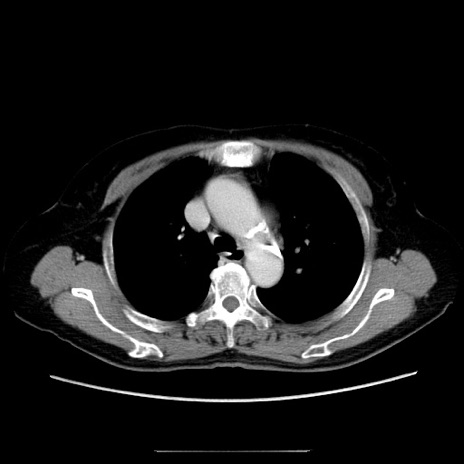

冠状断像

症例5(横断像)

【症例】70歳代女性

【主訴】お腹が張る

【現病歴】1週間くらい前から腹部膨満の自覚あり。昨日夜から増悪したため、本日救急外来受診。

【身体所見】意識清明、BT 36.5℃、BP 165/106mmHg、HR 80bpm、SpO2 98%、腹部:膨満、軟、自発痛・圧痛なし、触診にて不快感あり、腸蠕動音:減弱

【データ】WBC 12600、CRP 1.04